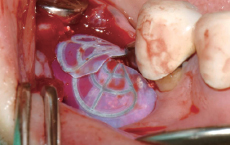

Wifi-Mesh 준비

Wifi-Mesh 형태 형성 *

Wifi-Mesh 장착

* 확실히 구부려 형태를 형성하여야 하며, 불완전하게 구부릴 경우 치은 안에서 벌어질 수 있습니다.